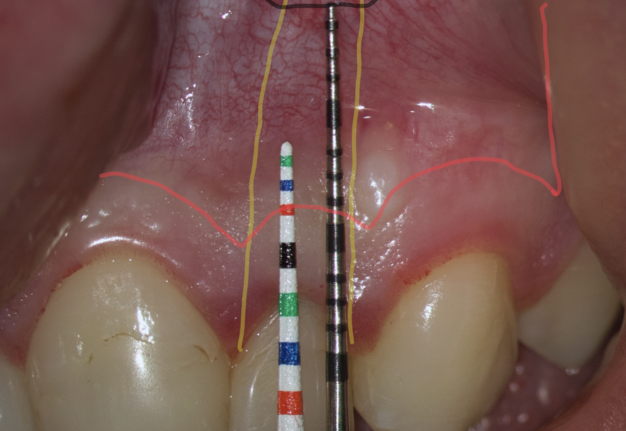

The most popular paramarginal or submarginal flap is the one designed by Clifford Ochsenbein and Raymond G. Luebke (1974) [4, 5]. The Ochsenbein-Luebke flap is formed by a scalloped horizontal sub-marginal incision placed within the attached gingiva, which follows roughly parallel to the contour of the gingival margin. The horizontal incision continues with two vertical releasing incisions [6]. These vertical incisions extend from a point 1 to 2 mm short of entering the mucobuccal fold to a point on the attached gingiva approximately 3 to 5 mm above or below the marginal gingiva and the sulcus depth (Figs 1 and 2) [7, 8].

The submarginal flap is only to be used, when there is a broad zone of attached gingiva with a minimum of 2 mm [9]. The width of the attached gingiva is then calculated on the basis of the distance from the base of the sulcus to the linea girlandiformis (mucogingival junction) [6]. Consequently, the incision must be placed at least 2 mm from the depth of the gingival sulcus. Extensive periodontal probing should be done to establish the depth of the gingival sulcus before the incision is made [10]. Periodontal probing should be conducted not only around the causative tooth but also in the adjacent teeth.

We transfer this distance is transferred to a metal probe and fixed with an endodontic stopper. Next, we take a plastic probe and substitute it near the zenith of a tooth on which the intervention will be performed at a mark of 6 mm (3 mm must be retreated to perform a submarginal incision and another 3 mm is needed for the formed flap to overlap healthy bone tissue) (Fig 8).

We compare the lengths of the plastic and metal probes. The first option is when the metal probe is above the plastic one, then we can assure that the incision and the Ochsenbein-Luebke flap will accurately cover the bone defect and the submarginal incision is safe (Fig 9).